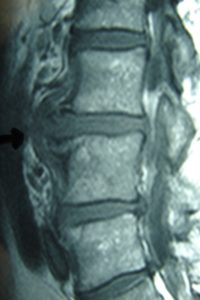

Μαγνητική Τομογραφία-Ακολουθία Τ1 και Τ2 της Ο.Μ.Σ.Σ. γενόμενη προ της εισαγωγής του στις 04/06/2007.

Οβελιαία τομή (α,β). Καταδεικνύεται η εκφύλιση του μεσοσπονδύλιου δίσκου στα επίπεδα Ο3-Ο4, Ο4-Ο5 και Ο5-Ι1 με μικρή οπίσθια προβολή ιδιαίτερα στο επίπεδο Ο3-Ο4. Ωστόσο στο επίπεδο αυτό είναι εμφανής η πρόσθια αποστηματική συλλογή.

Μετωπιαία τομή (γ,δ) Δεν είναι εμφανής η ύπαρξη της αποστηματικής συλλογής ωστόσο στο επίπεδο Ο3-Ο4 (Α) πιθανολογείται η ύπαρξη μάζας η οποία προκαλεί απώθηση του υοϊτού μυός.

Εγκάρσια τομή (ε,ζ) Είναι σαφής η ύπαρξη προ και παρασπονδυλικής αποστηματικής συλλογής και σε μικρότερο βαθμό οπισθίως εντός του σπονδυλικού σωλήνα.